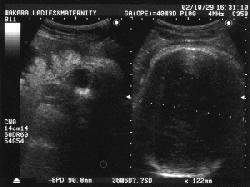

続いて、超音波。(ビデオテープ持ってくの忘れた…)

最後の超音波写真。左半分が横顔。目玉しかわからん。

BABYも胎盤も羊水もなんの問題もなし。